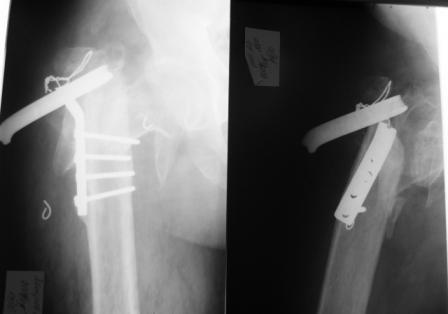

Доброго времени суток! В клинику обратился пациент П., 40 лет с несросшимся чрезвертельным переломом левого бедра, состояние после остеосинтеза Г-образной пластиной, перелом фиксатора.

Из анамнеза известно, что травма в 2004 году - лечился консервативно. В течение 2 -х лет наблюдался у травматолога по месту жительства - перелом не сросся. В 2006 году пациенту выполнен остеосинтез несросшегося чрезвертельного перелома левого бедра Г-образной пластиной.В течение 3 -х лет пациент ходил с дозированной нагрузкой на оперированную конечность. В ноябре 2009 года почувствовал резкую боль в области операции, отмечал нестабильность, утрату опороспособности. При осмотре укорочение конечности 7 см. Коллеги, необходимы ваши рекомендации в лечении данного вида последствий травмы. На КТ диагноз подтвержден.